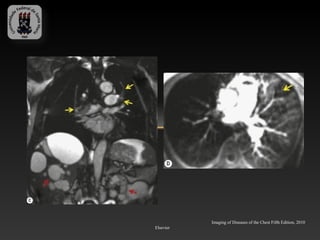

- Paciente masculino, 59 anos, com dispnéia severa e tromboembolismo em

artérias pulmonares e lobares

Imaging of Diseases of the Chest Fifth Edition, 2010

Elsevier